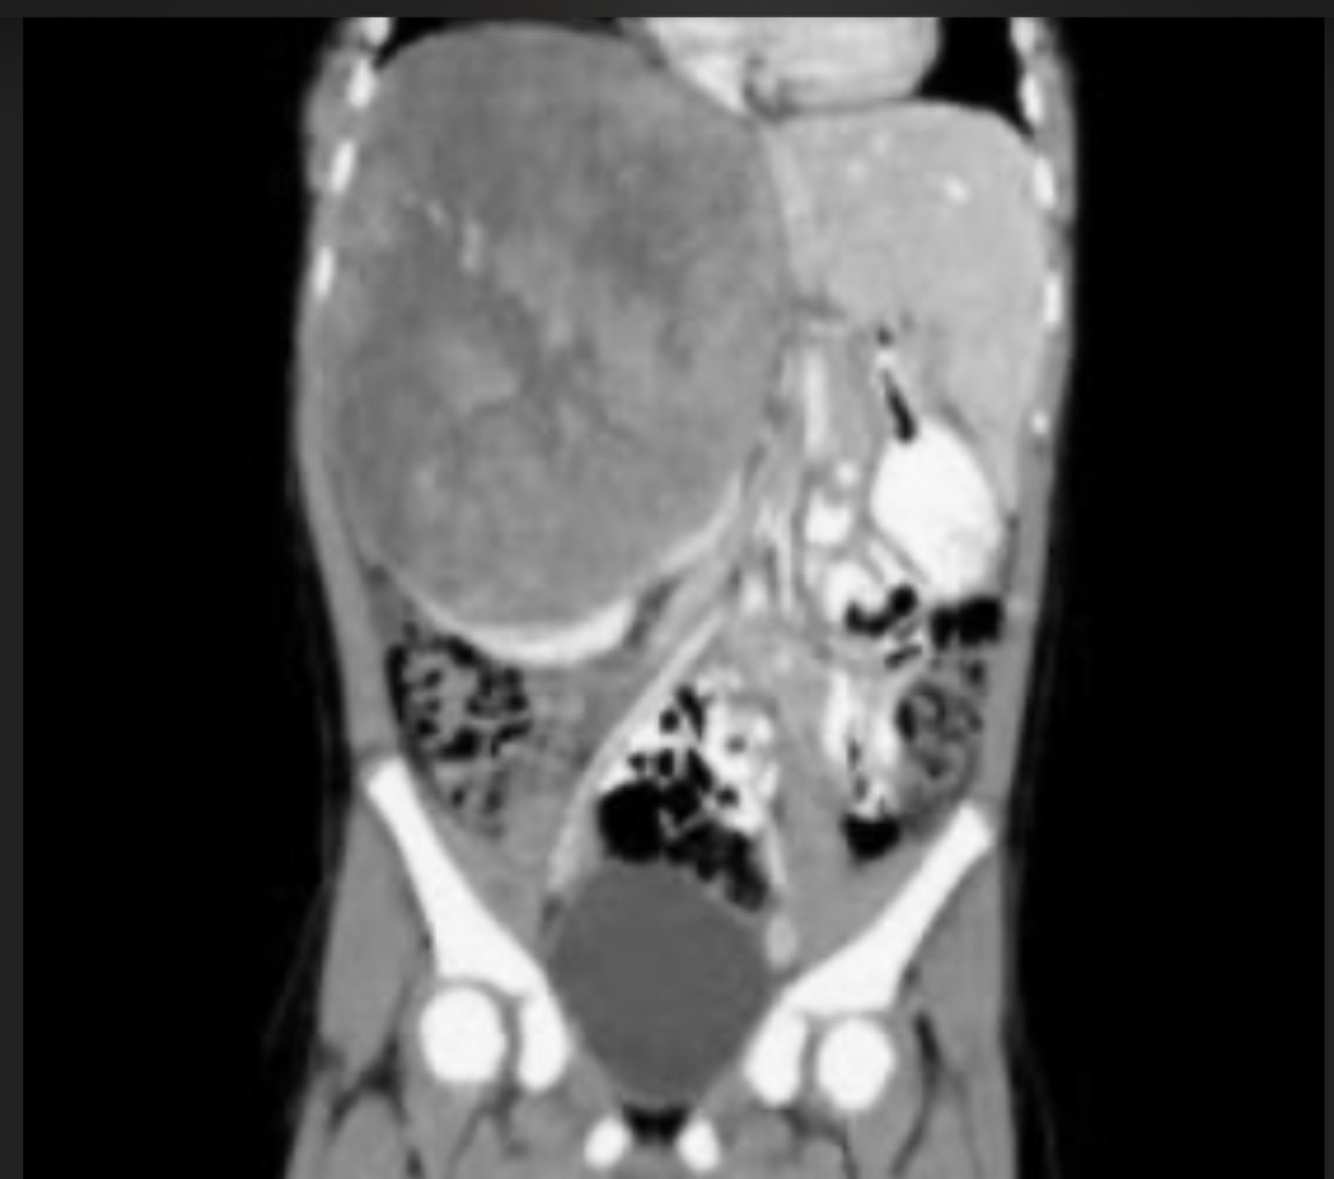

8

Q

-Tabaquismo +

-Astenia

-Adinamia

-Hiporexia

-Baja de 12 kg en cuatro meses

-Hematuria silenciosa

A

Cáncer renal